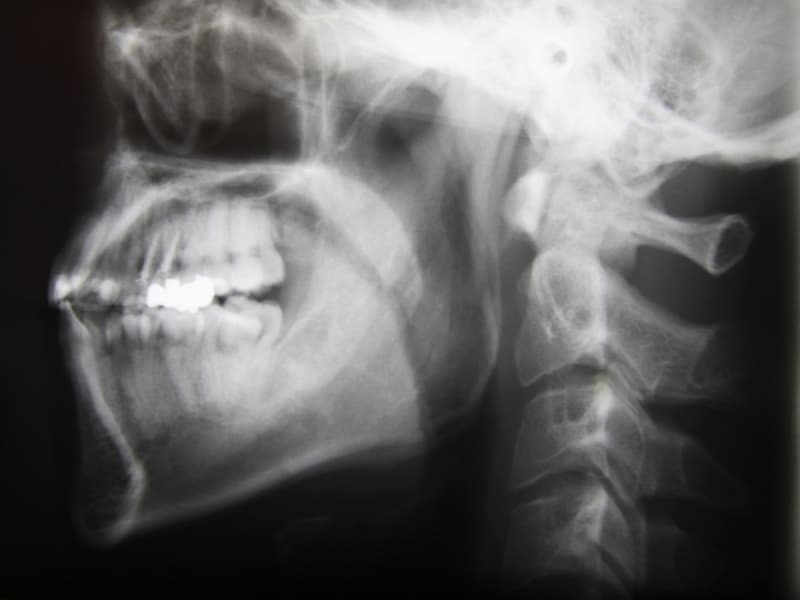

まず診査をおこない、診断→治療とおこないます。例えば、出っ歯の場合でも上あご骨自体が前に出ていて出っ歯なのか、上の歯が傾き出っ歯なのか、下あごが後ろに下がっていてその結果として出っ歯に見えるのかで治療法は異なります。とがし歯科医院では、どのような治療でも診査診断が一番大事であると考えています。

出っ歯

(上顎前突・下顎後退)

上の前歯が下の歯よりも出っぱっている場合に起こります。上の歯が出ている場合、下の顎が引っ込んでいる場合などに起こりますが、指しゃぶりの影響や幼児性嚥下(乳児期のおっぱいの飲み込み方が抜けない場合)の影響を強く受けます。まず、悪影響を与えている因子(癖など)の除去をおこない、それで十分でない場合には治療介入します。

受け口

(下顎前突・上顎劣成長)

下の歯が上の歯よりも前に位置し、かみ合わせが通常とは反対の場合に起こります。遺伝による影響がとても強く、比較的早期(乳児期)からの治療が必要です。親御さんや親類に受け口がいる場合は注意しましょう。日常生活では奥歯で良く噛むようにしましょう。